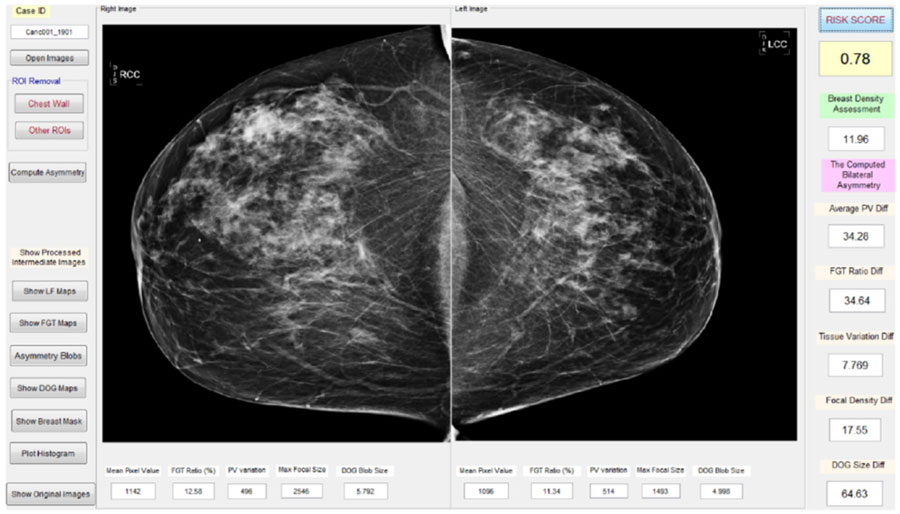

评估计算机辅助诊断乳癌性能

近20年来,在计算机数字图像处理和机器学习技术飞速发展帮助下,用于图像、分类诊断乳腺癌技术大有改善。自1990年代计算机辅助诊断技术开发初期以来,匹兹堡大学和俄克拉荷马大学的本郑教授就致力于研究评估自身能力工作允许提高从确认到成功先检测癌症 从数字化乳房X线图到使用MRI评估乳房肿瘤对化疗响应.